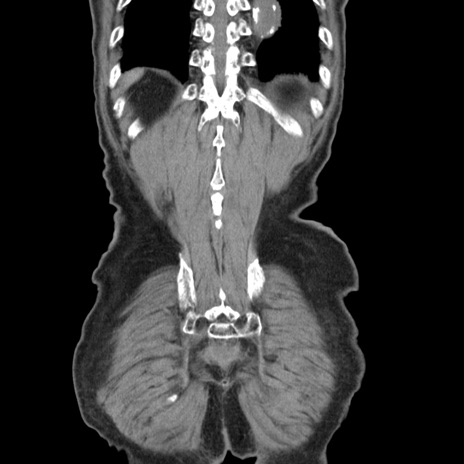

症例24(冠状断像)

【症例】80歳代男性

【主訴】左側腹部痛、嘔吐

【現病歴】本日早朝より左腹部に痛みあり。昼頃嘔吐認めたため、救急要請。

【既往歴】直腸癌(Mile手術)、胆摘

【身体所見】意識清明、BT 35.9℃、BP 221/93mmHg、SpO2 97%(RA) 、腹部:左ストーマ周囲に限局性の腹部膨隆あり。 膨隆部自発痛・圧痛あり・軟。

【データ】WBC 7700、CRP 0.09